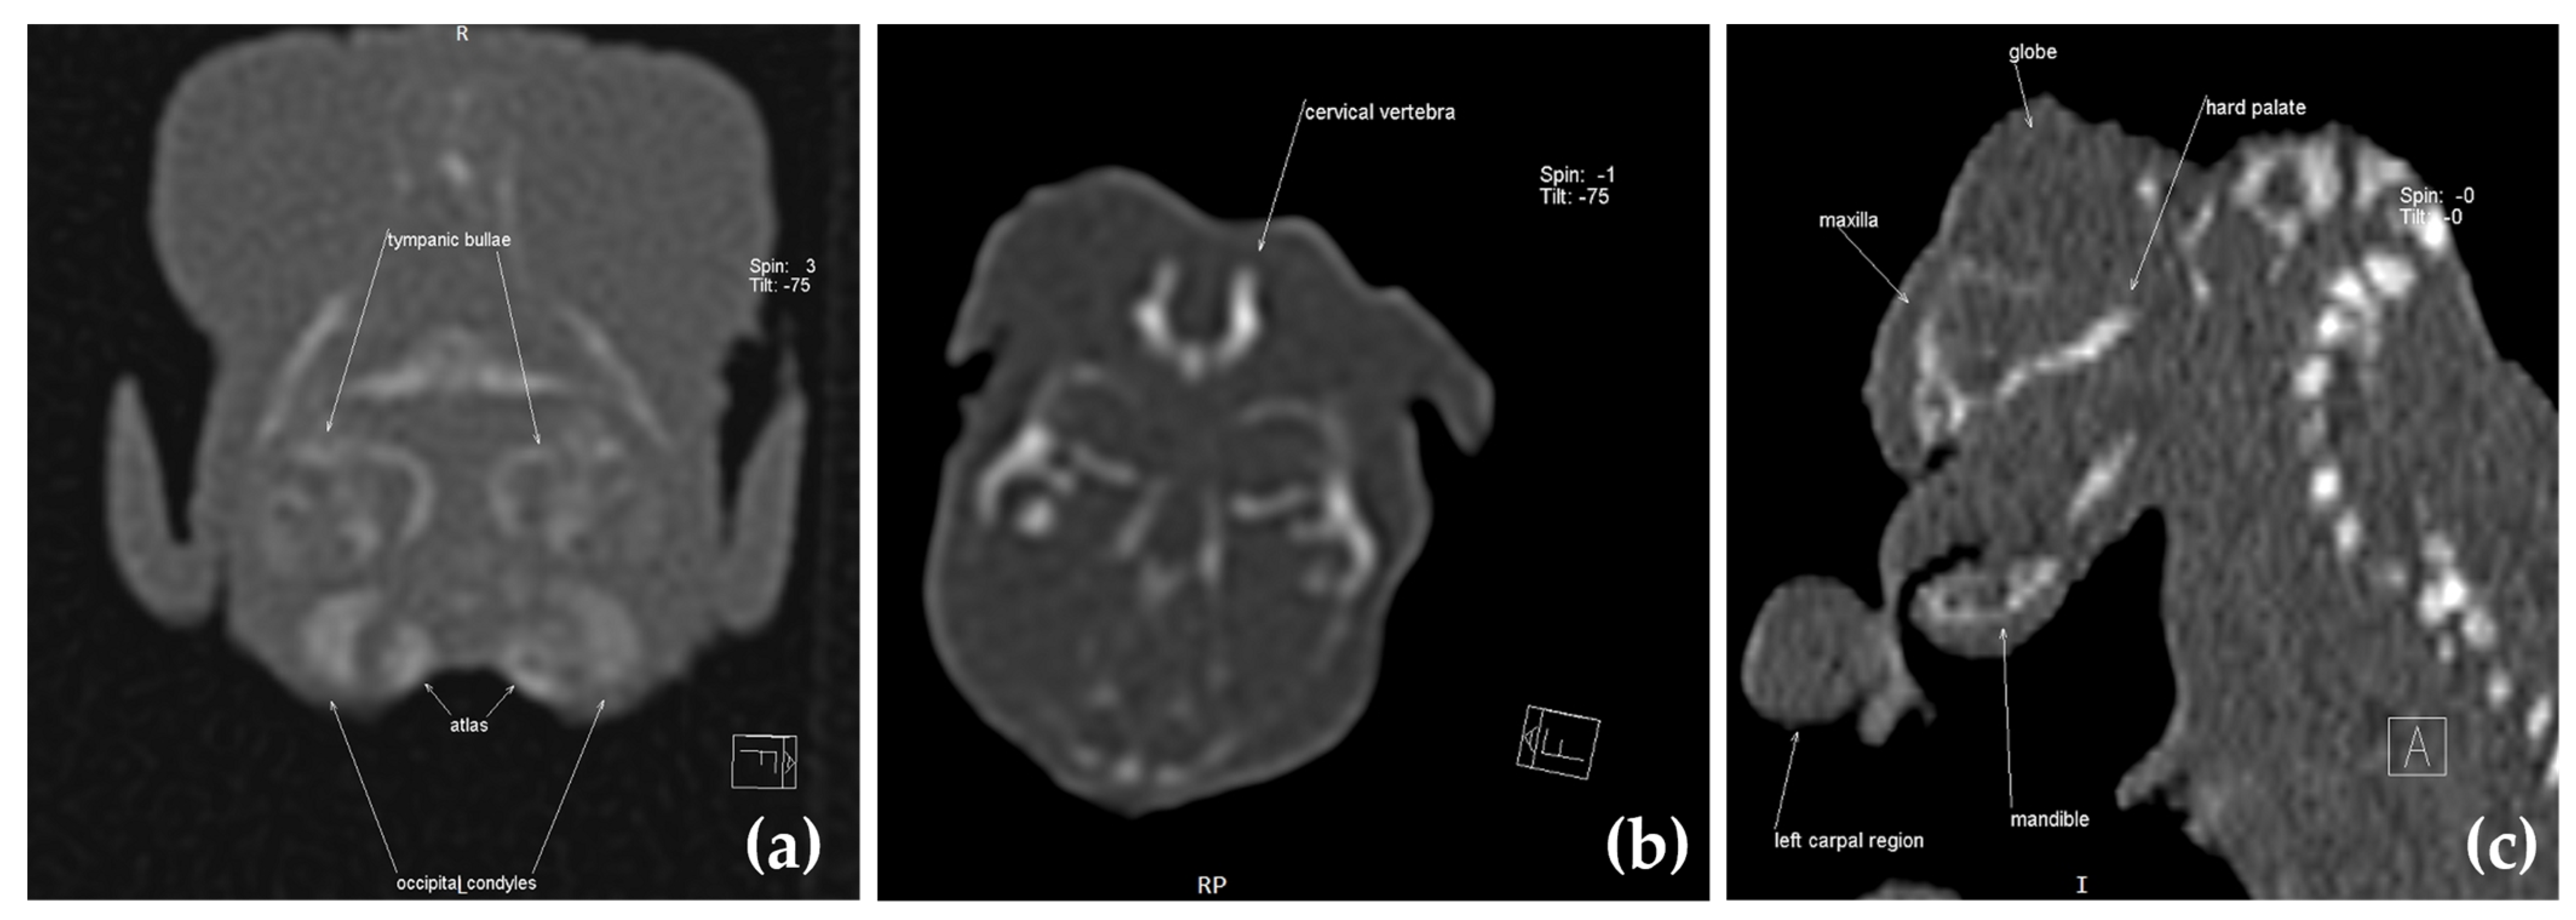

2.3. Computed Tomography Investigation